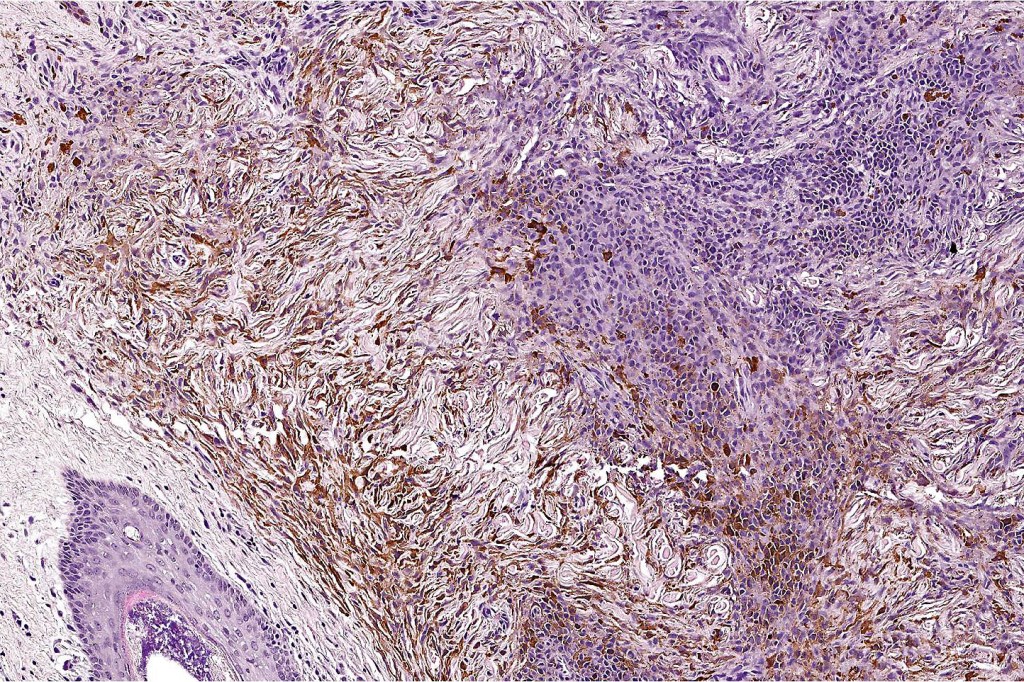

Combined common melanocytic nevus & BAP1-inactivated melanocytoma